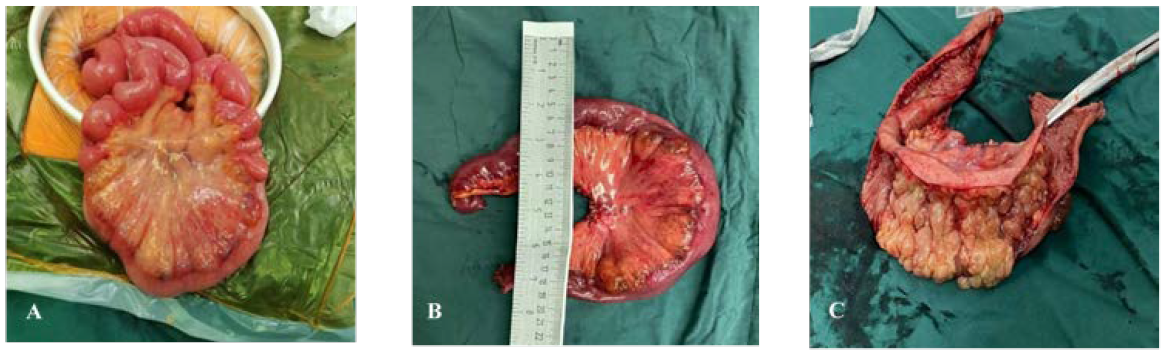

Patient B, a 52-year-old woman, went to the hospital on 3 November 2020 because of “recurrent upper abdominal pain for more than 20 days”. The patient had abdominal pain more than 20 days ago. The pain was mainly in the middle and upper abdomen, which was like a paroxysmal knife cutting and relieved after several seconds. There was no radiating pain in the waist and back, no abdominal distension, and no nausea and vomiting. Physical examination showed tenderness in the middle and right upper abdomen without rebound pain and muscle tension. The abdomen is flat without gastrointestinal type or peristalsis wave, there was no obvious mass, and the bowel sounds are normal. Admission diagnosis revealed abdominal pain of unknown origin. There were no abnormalities in blood routine, CRP, biochemistry, AFP, CA19-9, and CEA. Abdominal enhanced CT showed local intestinal wall edema, structural disorder, and mesenteric edema, as shown in Figure 4. Esophagogastroduodenoscopy revealed bile retention fluid in the stomach. Capsule endoscopy showed ileal lesions, with multiple continuous nodular changes in the mucous membrane, and the surface was red and erosive, as shown in Figure 5. Contrast-enhanced CT of the small intestine showed segmental intestinal wall thickening in the terminal ileum with obvious edema of the surrounding mesentery, which suggested the possibility of inflammatory bowel disease (IBD). CT three-dimensional reconstruction of small intestine showed segmental intestinal wall thickening in the distal ileum with obvious edema in the surrounding mesangium. After consultation with the imaging department, the patient was suspected to have Crohn’s disease (CD) due to the ileal lesions. However, the clinical features and course of the patient did not conform to the typical manifestations of CD, so surgical treatment was important for diagnosis and treatment. The patient underwent surgical treatment on 1 December 2020. Intraoperative exploration revealed a 30-cm-long part of the small intestine with obvious edema and thickening 4.5 m away from the ligament of Treitz. The intestinal lumen was narrow and the mesangial surface was uneven, showing cystic jelly-like changes. During operation, the operator dissected a piece of intestine with a length of 38 cm and a diameter of 4–7 cm. There is an 11 cm × 7 cm mucous bulbous area 6.5 cm away from the cut end on one side and 15 cm from the cut end on the other side. The mesenteric surface was hard in texture, and the cut surface was spongy and gray yellow, as shown in Figure 6. Pathology indicated small intestinal lymphangioma, and no cancer involved both ends, as shown in Figure 3. After the operation, she left the hospital after receiving anti-inflammatory and nutritional support therapy.

Figure 6 Surgical excision of gross specimen for patient B. (A) Diseased bowel piece; (B) cut a section of bowel intraoperatively, with a length of 38 cm and a diameter of 4–7 cm; (C) 6.5 cm from the end of one incision and 15 cm from the end of the other, a mucous vesicular uplift area of 11 cm × 7 cm can be seen. The mesentery surface is hard in texture, and the section is spongy and gray yellow.